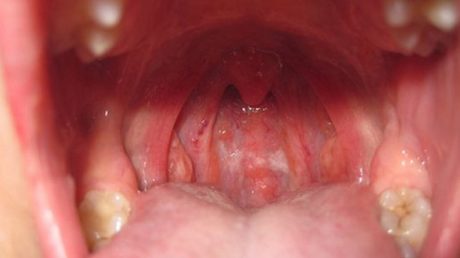

Viêm họng mãn tính có chữa khỏi không là câu hỏi nhiều bà con thắc mắc. Tuấn tôi hiểu rằng bệnh này không dễ chữa...